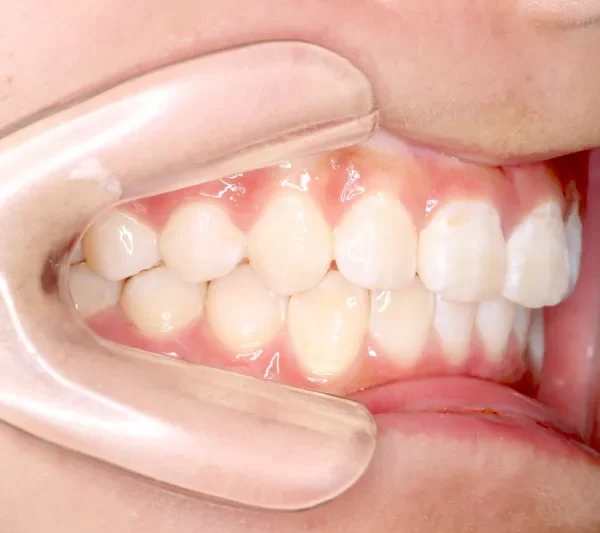

• 治療終了後

治療終了後

治療回数43回、7年4ヶ月の治療期間で矯正治療を終了しました。

主訴が改善され、ご満足頂きました。